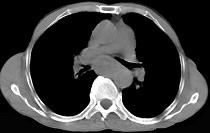

问题 女性患者,67岁进行性吞咽困难半年,X线及CT检查如图,应诊断为 ( )

选项 A.食管癌 B.食管憩室 C.食管炎 D.食管良性狭窄 E.食管静脉曲张

答案 A